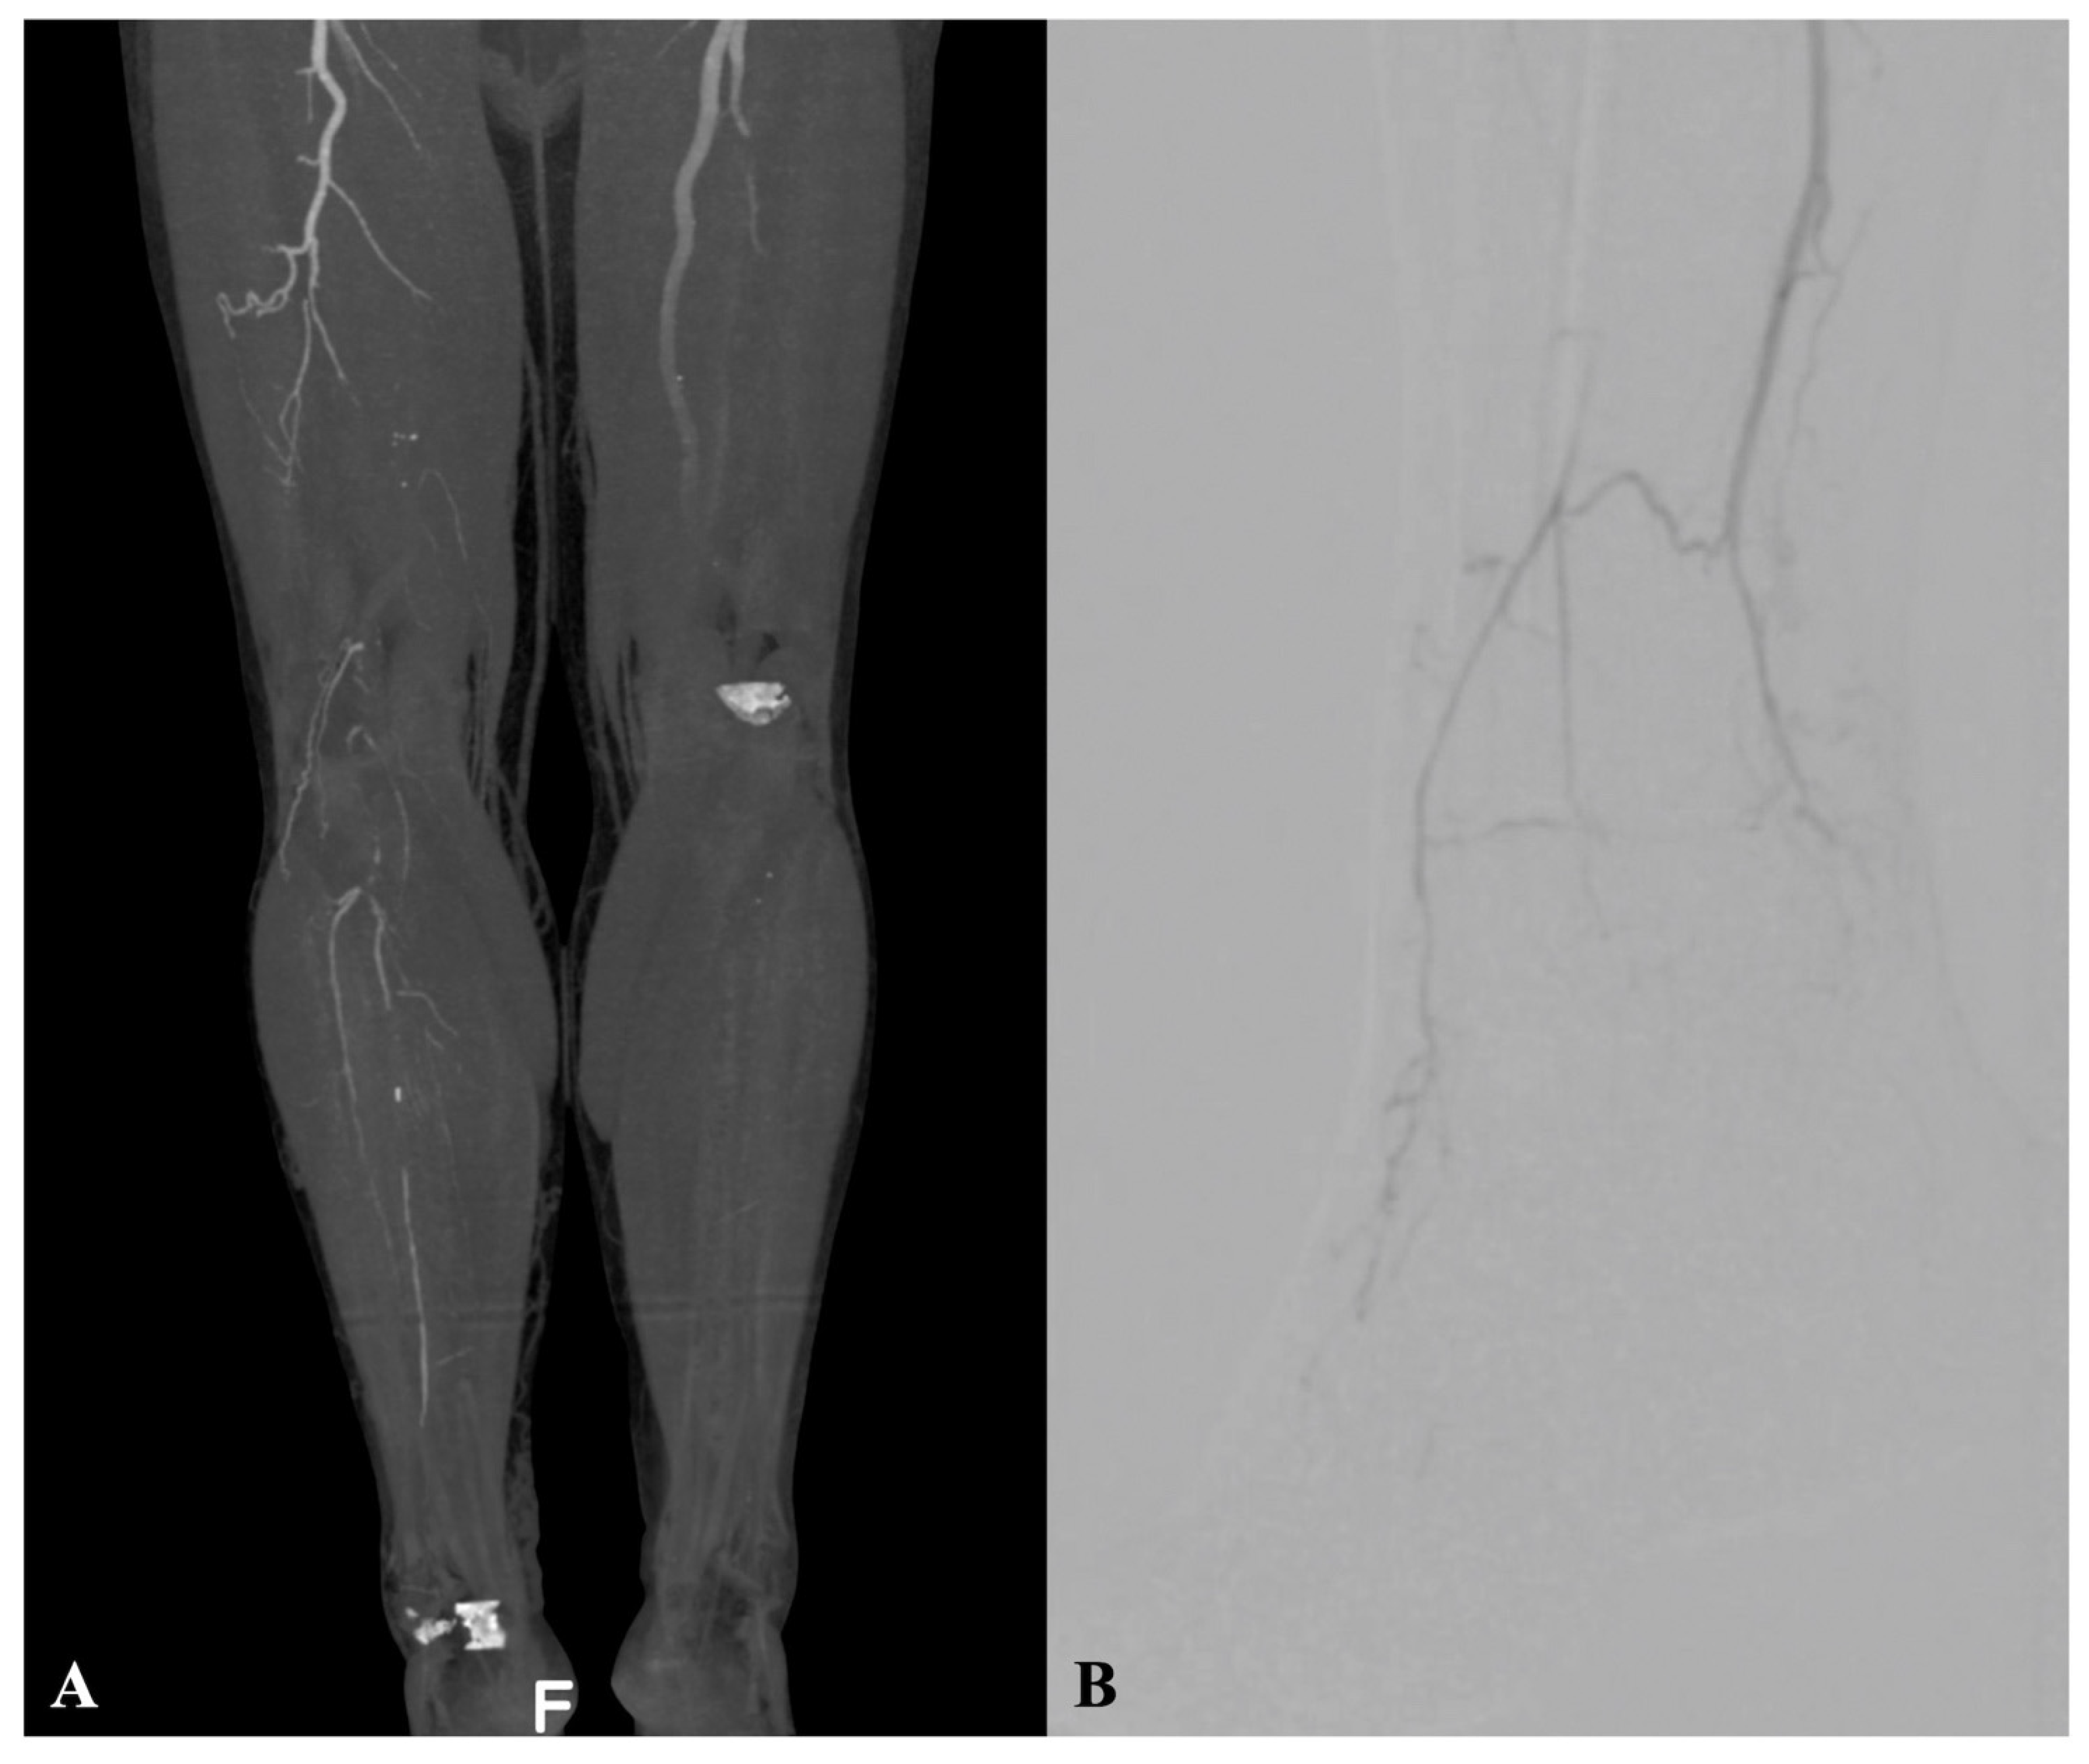

The pre-operative assessment comprised clinical evaluation, ankle-brachial index (ABI), transcutaneous oximetry, and Doppler ultrasound examination. Selective computed tomography angiography or arterial angiography were performed pre-operatively (

Figure 1A,B).